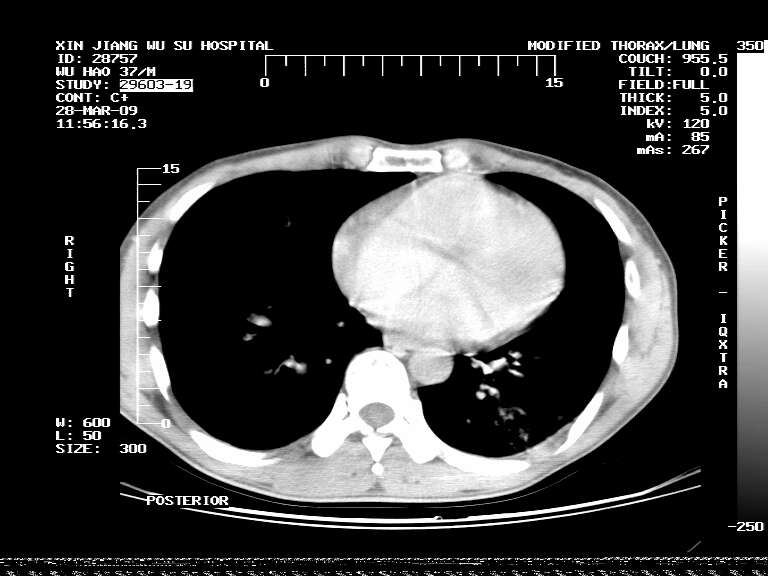

男,37岁,体检胸透发现阴影。

患者体检发现 无症状 左肺下叶占位,边缘模糊,可见血管聚束、分叶、胸膜牵拉,增强呈不均匀性强化。 首先考虑左肺下叶周围型肺癌,建议穿刺活检。

左肺下叶见一结节病变,边缘欠清不光滑,与胸膜粘连且胸膜局限性增厚,注药后呈环形强化,动脉期壁呈明显点环状强化,静脉期壁强化减低,中心密度低无强化,灶周无明显的卫星灶和水肿区(晕征)---考虑周围性肺癌,不除外感染性病变,建议穿刺活检。

左肺下叶软组织病灶,密度较高,内见点状钙化,其周围见子灶,邻近胸膜扁平样增厚.c+病灶强化明显,中心强化弱.诊断:左肺下叶结核瘤.

左肺下叶大片实变影,内靠胸膜见不规则更高密度结节灶,边缘强化,相邻胸膜增厚,胸膜下脂肪线存在。考虑炎症,结核可能。